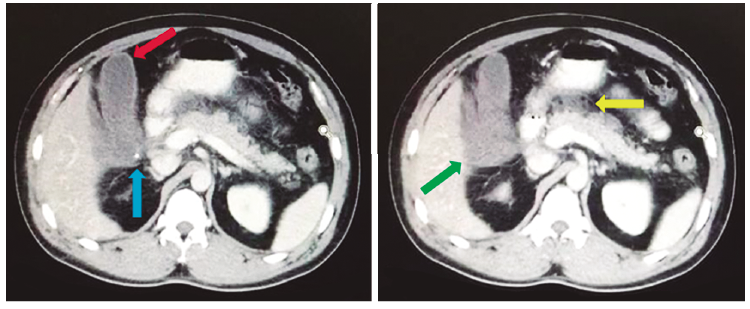

Tomografía computada con reconstrucción axial de abdomen con contraste oral y endovenoso (Figuras 1 y 2). Se observa vesícula distendida de paredes engrosadas con contenido heterogéneo (flecha roja), borramiento de la pared posterior a nivel del bacinete, englobada en plastrón inflamatorio (flecha verde). Signos de perforación vesicular. Se observa imagen litiásica calcificada excéntrica al contorno parietal (flecha azul). Páncreas edematoso con colecciones peripancreáticas (flecha amarilla).